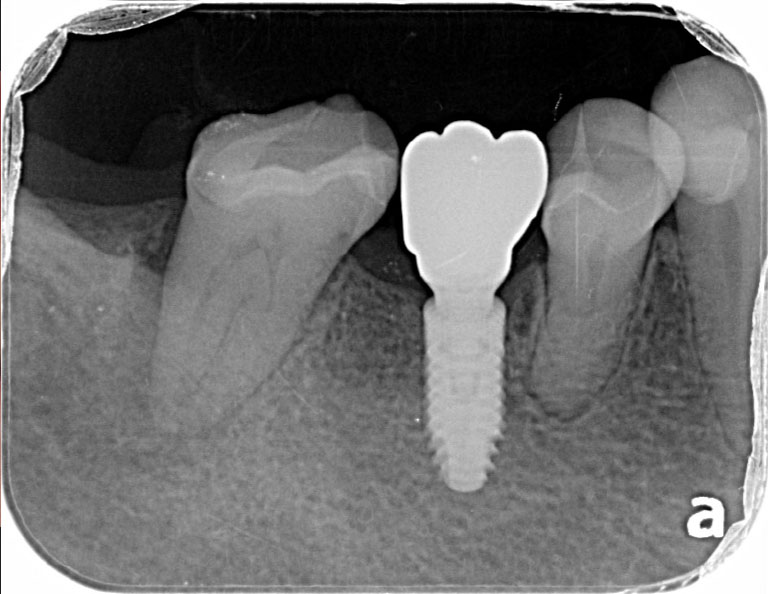

術前のレントゲン写真です。

根管治療後のレントゲン写真です。